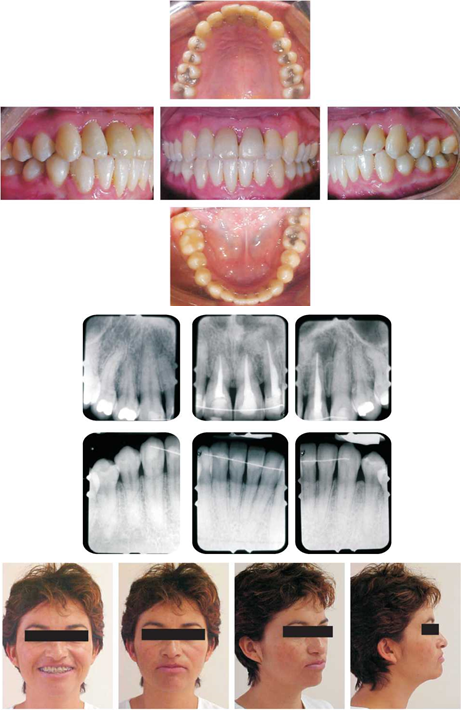

El resultado del caso, obtenido a los 16 meses de tratamiento, en cuanto a las relaciones interdentales se logró obtener una clase I molar y canina, una forma de arcadas correspondientes (ovoidales) y una sobremordida horizontal aceptable.

Periodontalmente la respuesta fue positiva, esto se puede corroborar con el sondeo periodontal obtenido un año postratamiento comparado con el referido pretratamiento (Cuadro I). Por otro lado, al observar las radiografías periapicales pre y postratamiento, es importante notar la remodelación positiva de las crestas óseas, sobre todo a nivel de los dientes anteriores superiores; esto se corrobora con el color rosa pálido de la encía y la ausencia de sangrado y fluido crevicu-lar. En el aspecto facial no se presentaron cambios de importancia; si bien la proquelia superior se esperaba por la proinclinación de los incisivos, la expresión de sonrisa mejoró notablemente (Figura 5). En el sentido cefalométrico se alcanzaron los objetivos esperados considerando que se trató de un caso compensatorio (Cuadro II y figura 6).

Figura 5 Se observan fotografías intraorales con relaciones caninas y molares en Clase I, líneas medias coincidentes y sobremordida vertical y horizontal aceptables, la encía se observa de color rosa pálido y sin sangrado. Las radiografías periapicales demuestran la remodelación positiva de las crestas marginales tanto en dientes superiores como inferiores. Las fotografías extraorales definen la proyección facial final.